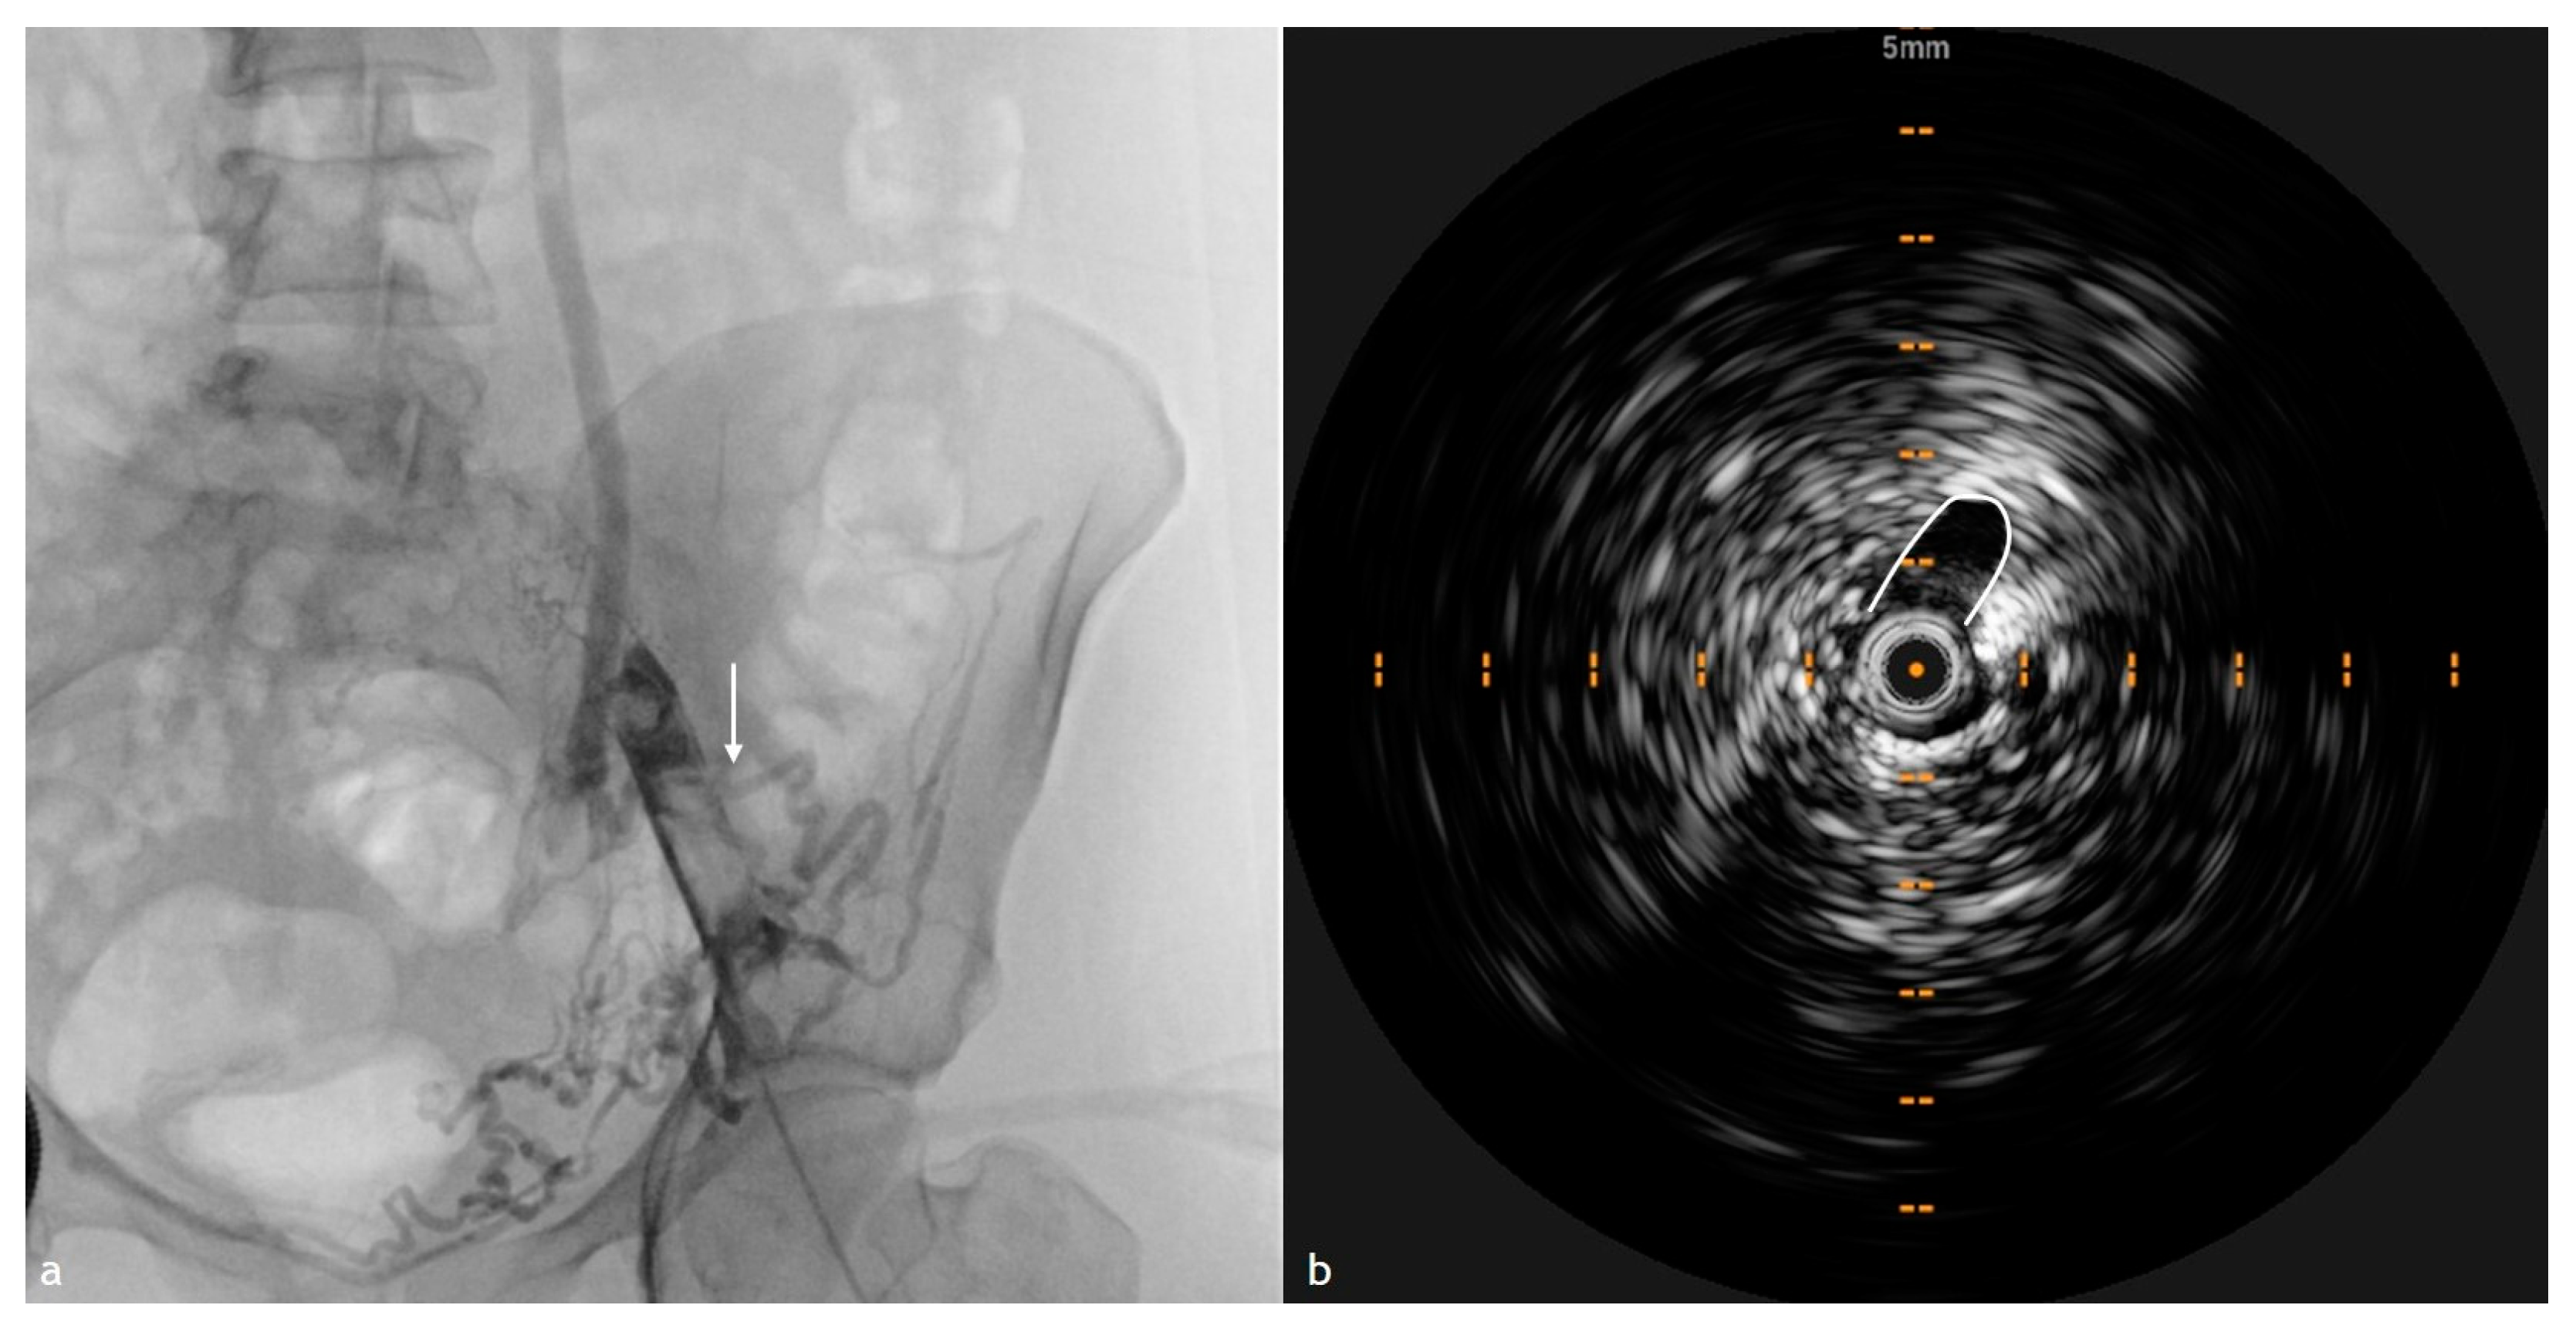

4. IVUS in PTS